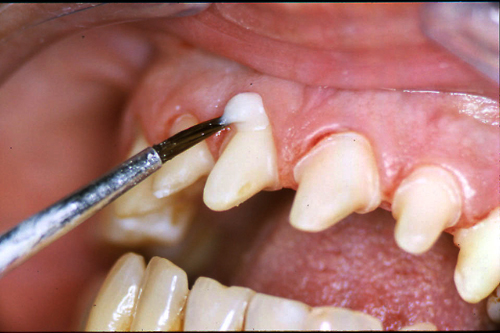

ABSTRACT El Bruxismo es una entidad patológica en la que concurren diferentes factores. Entre ellos el stress que conlleva consigo la vida moderna, constituye el Factor Predisponente sobre el que se ha abundado en innumerables tratamientos de tipo general, actuando sobre la psiquis y el comportamiento del individuo, ya sea con fármacos o bien mediante medios psicológicos. Sin embargo, como tantos desequilibrios provocados por el stress, confluyen siempre con un Factor Desencadenante, que en el caso del Bruxismo se encuentra en las desarmonías entre los componentes varios del Sistema Estomatognático. DESARROLLO Paciente varón, de 43 años, constitución atlética. A la inspección se observan desgastes oclusales que alcanzan la calidad de Facetas Parafuncionales, con dentina expuesta y empastes totalmente gastados y evidentes signos de falta de Disclusión Canina de ambos lados. Sobre dicho montaje se realiza un Encerado Progresivo de Diagnóstico, aportando en el mismo los elementos necesarios para obtener todos los principios básicos de una Oclusión Orgánica. FIG. 6 a 24 Una vez aprobado el fisiologismo de la oclusión en el articulador, se reproducen modelos de yeso con la nueva situación, y se estampa un SET UP en cada maxilar. FIG. 25/26 Procedemos entonces al tallado de las piezas correspondientes a la Guía Anterior, y rebasamos los estampados, creando en boca una nueva situación desoclusiva, que permanece en boca durante los pocos días que transcurren entre la primera y segunda visita de trabajo. FIG. 27/33 Ya abordando en esta segunda visita los sectores posteriores, tanto superiores como inferiores, tallamos siempre de manera supragingival, destacando la importancia vital de la forma obtenida en las provisionales, a las que abrimos plenamente las troneras para lograr una correcta higiene. FIG.34 a 43 FIG. 44 a 52 Efectuados los colados en oro y probados en boca, en el laboratorio se confecciona el bizcochado de la nueva Guía Anterior, la que puede o no copiarse de la Guía Anterior provisional, mediante la técnica denominada Trayectoria Funcionalmente Generada, que consiste en realizar en la platina del articulador un registro estereográfico sobre acrílico Duralay en polimerización. FIG. 57/58 Ajustados todos los detalles mediante esta técnica, se instala en boca en forma Provisional y se deja funcionando una semana o dos, al cabo de las cuales se chequean las disclusiones , los ajustes, la eficacia masticatoria, la carencia de sintomatología articular y muscular. FIG.59 a 63 PIE DE FOTO FIG.9 OBTENCIÓN DE LA GUÍA ANTERIOR FIG.10 Y 11 PITOMBOS. ALINEAC. TRIDIMENSIONAL FIG.12 PITOMBOS. DISCLUSIÓN DER. FIG.13 PITOMBOS. DISCLUSIÓN IZQ. FIG.14 WILSON INF. FIG.15 WILSON SUP. FIG.16 BOCA DE PEZ INF. FIG.17 BOCA DE PEZ SUP. FIG.18 VISTA OCLUSAL FIG.19 O.R.C. FIG.20 DISCLUSIÓN DERECHA FIG.21 CRESTAS TRIANG. INT. FIG.22 CRESTAS TRIANG. INT. FIG.23 CRESTAS TRIANG. INT. FIG 24 CRESTAS TRIANG. INT. FIG.59 DISCLUSIÓN IZQ. FIG.60 DISCLUSION IZQ. FIG.61 DISCLUSIÓN DER. FIG.62 DISCLUSION DER. FIG. 63 AJUSTE PERIFÉRICO

Asiste a la consulta preocupado por sensibilidad dentaria ante el frío y el calor y por decoloraciones blanquecinas en sus dientes anteriores.

Con síntomas dolorosos y dinámicos en la ATM, con un estado periodontal sano y marcadas hipertrófias maseterinas.

Su condición de “borde a borde” también impide la disclusión en propulsiva, compartiendo en todas las excursiones las fuerzas con las piezas posteriores.